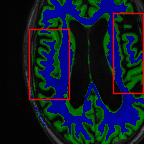

Sparsity LI 2D CNN 3D CNN Ours GT

4 Refer to caption (a) 0.6787/0.7972 Refer to caption (b) 0.8143/0.8776 Refer to caption (c) 0.8190/0.8714 Refer to caption (d) 0.8664/0.9085 Refer to caption (e) GM/WM

Refer to caption (f) 0.6808/0.7161 Refer to caption (g) 0.8103/0.8631 Refer to caption (h) 0.7950/0.8606 Refer to caption (i) 0.8598/0.9115 Refer to caption (j) GM/WM

8 Refer to caption (k) 0.5139/0.7240 Refer to caption (l) 0.6619/0.8224 Refer to caption (m) 0.6878/0.8584 Refer to caption (n) 0.7798/0.8853 Refer to caption (o) GM/WM

Refer to caption (p) 0.5910/0.6947 Refer to caption (q) 0.6516/0.8021 Refer to caption (r) 0.6507/0.8186 Refer to caption (s) 0.7471/0.8540 Refer to caption (t) GM/WM

Figure 6: Visual comparison of gray matter (Green)/white matter (Blue) segmentation over different methods, with respective DICE scores listed under the images.

In Fig. 6, we demonstrate the advantage of the proposed method in brain matter segmentation. It is clear that although 2D and 3D CNN generates visually plausible interpolation as presented in Fig. 5, the brain matters are easily misclassified due to incorrect anatomical structures and blurred details.